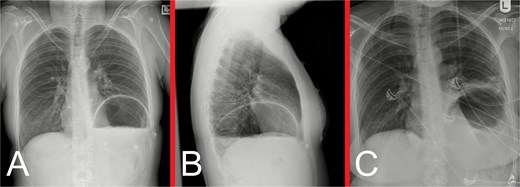

On initial examination, she was haemodynamically stable, with epigastric and left upper quadrant tenderness, but no peritonism. A venous blood gas showed a lactate of 2.7, but no acid–base disturbance or respiratory failure. Chest X-ray (CXR) revealed left hemidiaphragm effacement and a large air-fluid level in the left hemithorax (Fig. 1). A thoracoabdominal computed tomography (CT) scan revealed a markedly dilated stomach displaced into the left hemithorax, suggestive of a large, incarcerated left DH (Fig. 2). A nasogastric tube (NGT) was inserted for immediate gastric decompression (Fig. 1). An emergency gastroscopy confirmed a DH with displacement of the whole stomach into the chest. Endoscopic pyloric cannulation was impossible due to the herniated stomach’s configuration, but there was no mucosal damage, transmural necrosis, or gastric volvulus. Therefore, NGT decompression was continued as a temporizing measure, with planned semi-urgent definitive repair within a few days.

Representative CT images taken during the patient’s initial presentation. (A) Axial, (B) coronal, and (C) sagittal views illustrate a markedly distended stomach with an air-fluid level that is displaced into the left hemithorax, with normal mural enhancement and no evidence of gastric pneumatosis. The left lung is partly collapsed, but there is no evidence of an associated pleural effusion or pneumothorax. The free edge of the ruptured diaphragm is best appreciated on the sagittal view. These findings are consistent with a large, incarcerated left DH, with possible gastric volvulus.